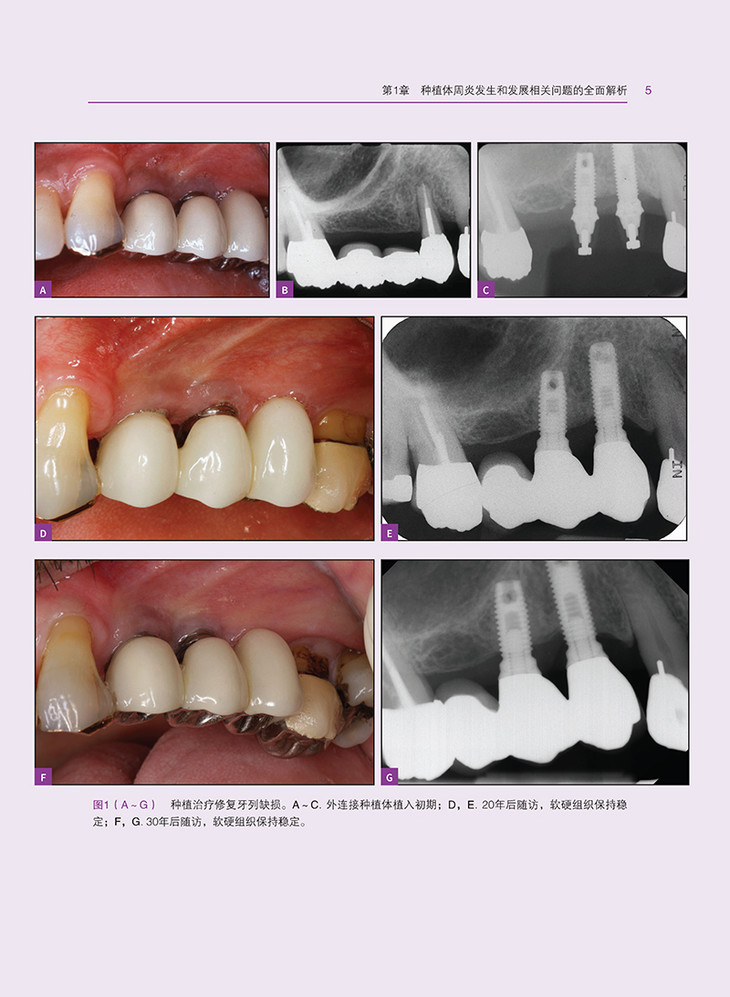

种植体周炎的发生和发展相关问题,从诊断与监测到治疗策略,涵盖了种植体周炎的各个方面。首先,深入探讨了种植体周炎的形态学和表型特征,为读者提供了清晰的认识基础。接着,详细分析了种植体周炎的理想三维软组织和硬组织量,以及影响种植体周炎的局部风险因素、全身因素和不良习惯。同时,本书还介绍了遗传学和表观遗传学对种植体周炎的影响,为深入理解种植体周炎的发病机理提供了新的视角。

在治疗方面,本书从初级预防和次级预防两个层面出发,详细阐述了种植体周炎的预防策略。同时,结合牙周炎治疗的经验,提出了种植体周炎的管理策略,包括非手术治疗、药物联合治疗和手术治疗等。此外,本书还介绍了种植体表面去污策略,以及手术治疗的时机选择,为读者提供了实用的治疗建议。